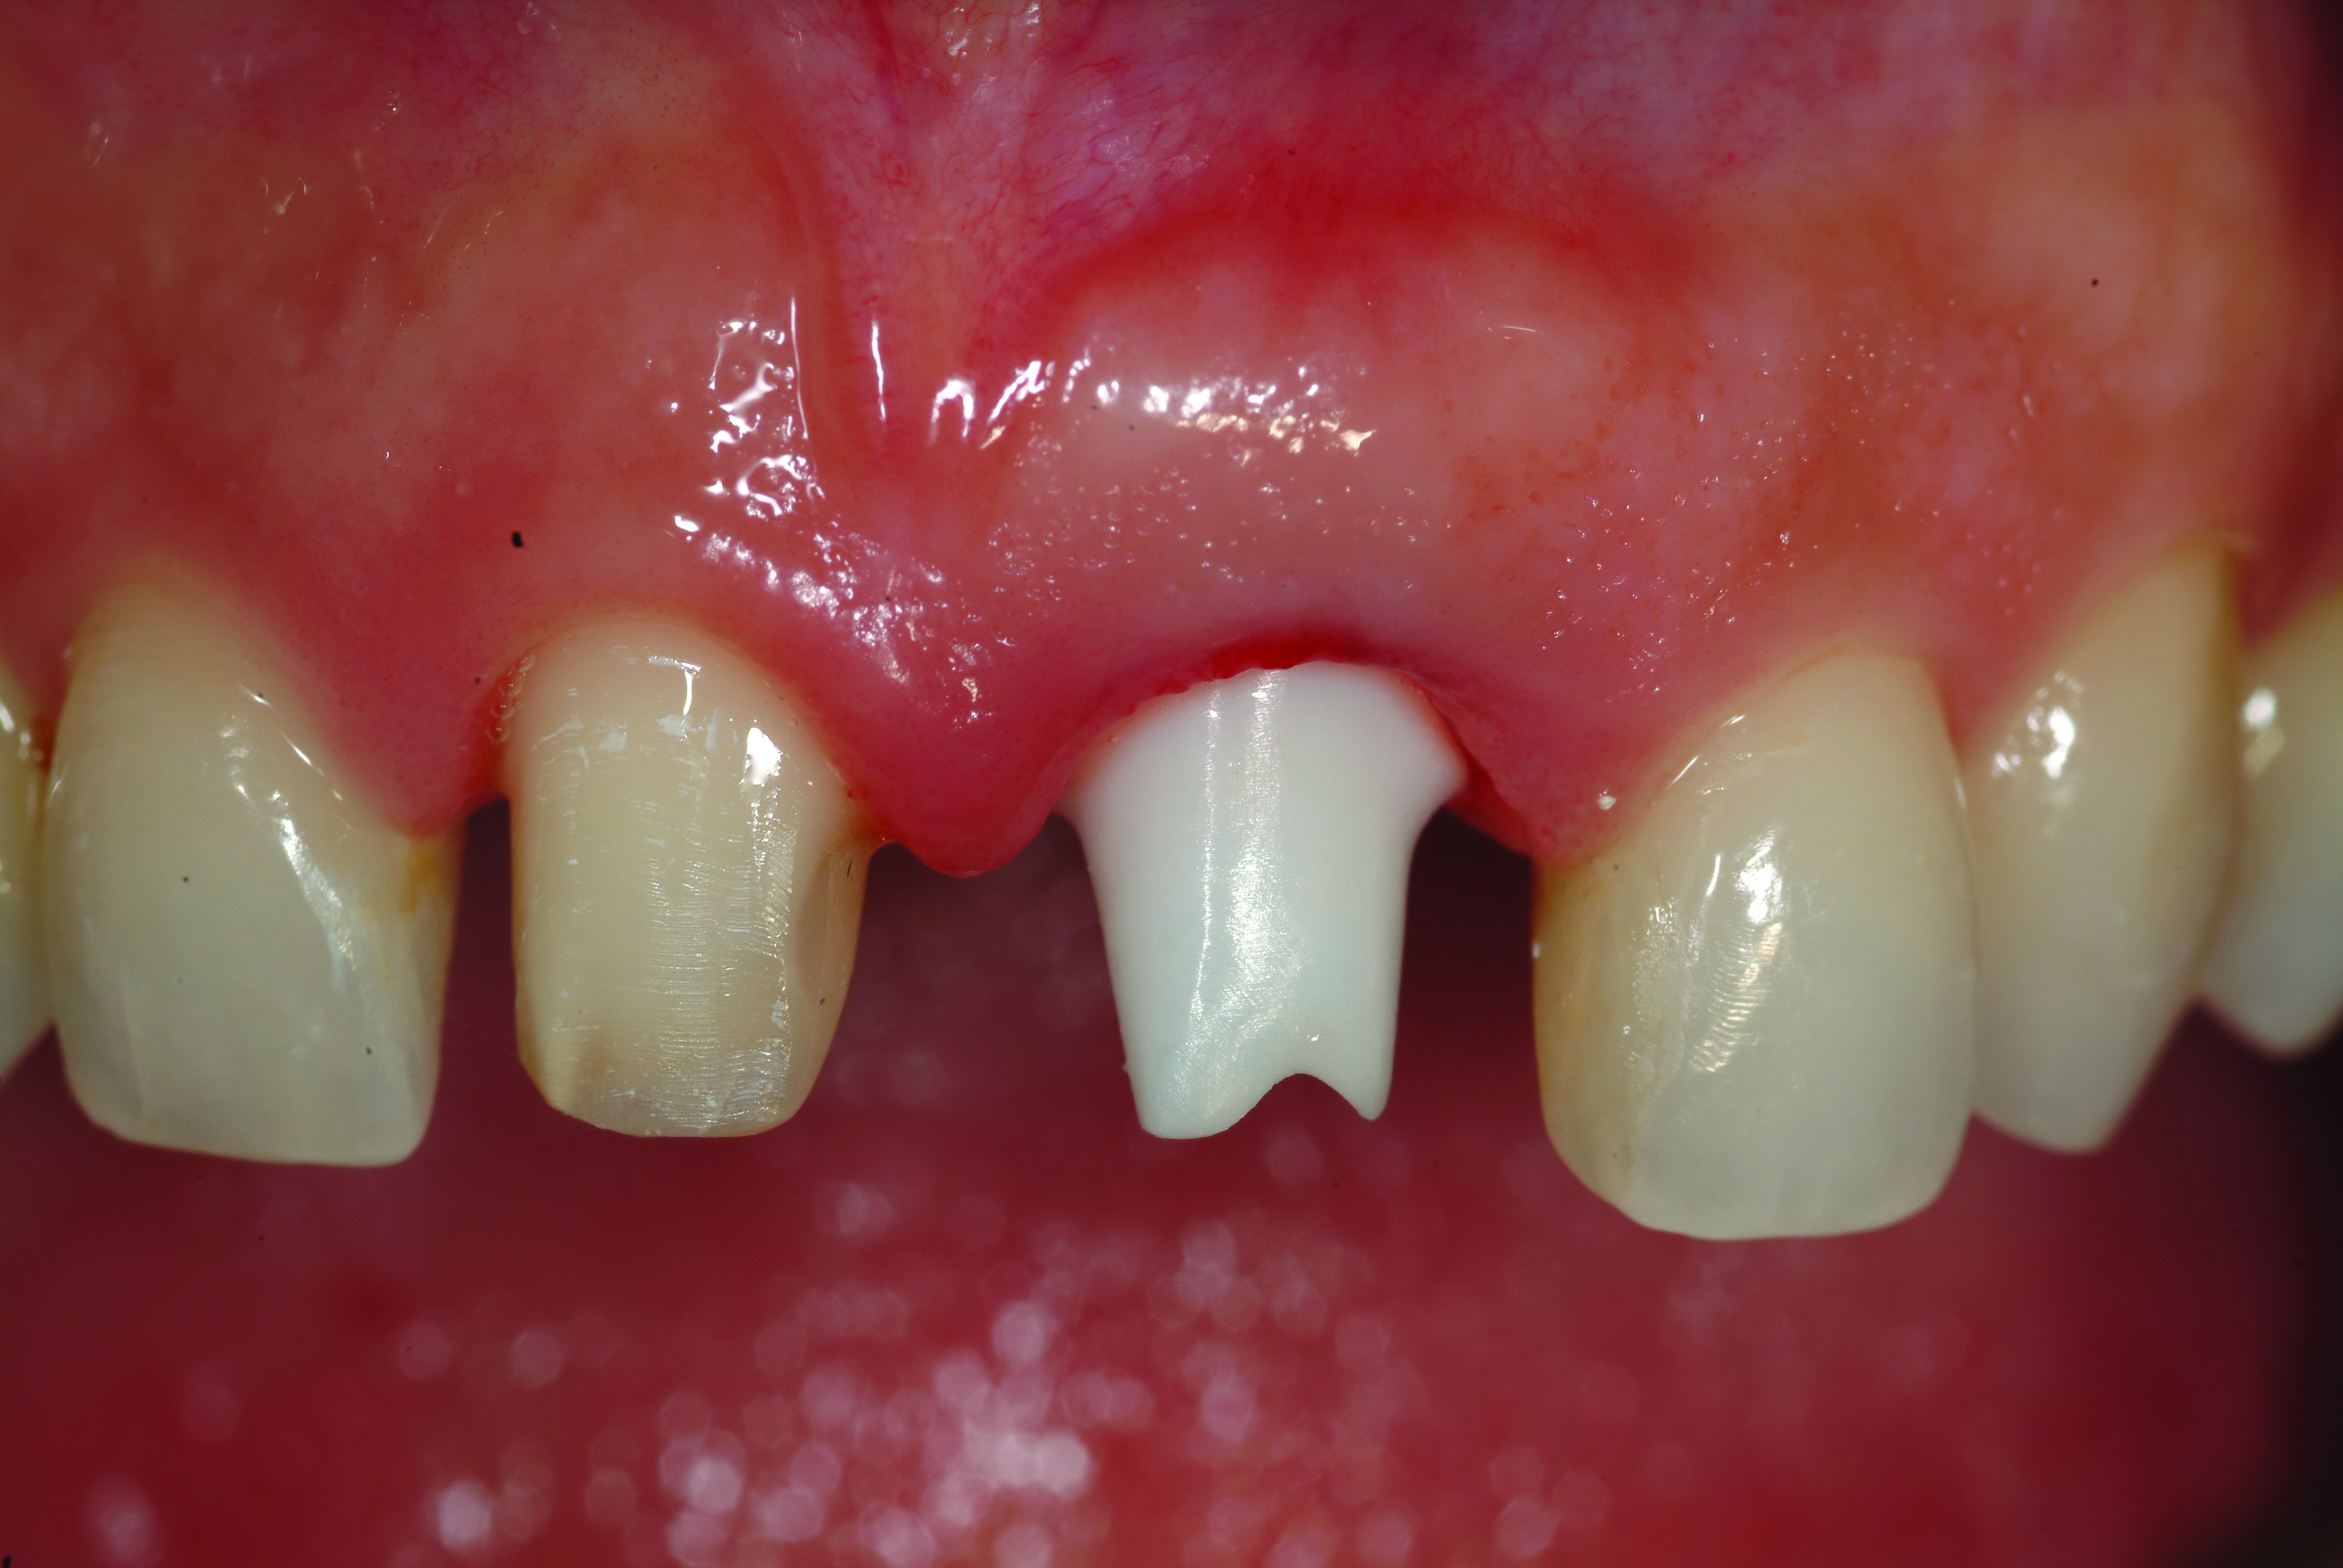

Fig 17. Preoperative view of the fractured No. 9.

Figure 17

Similarly, the approach of immediate implant placement and restoration is increasingly being used by clinicians, although the esthetic risks are considered high by some, because the procedure requires precision and careful management of hard and soft tissues. Aside from the patient-driven rationale for this approach, in appropriately selected cases, tissue guidance by the fixed restoration may lead to enhanced papilla development and better post-restoration facial tissue stability, because the soft tissues are less likely to slump or lose their anatomy. De Rouck and coauthors reported enhanced results with immediate versus delayed implant restoration.21 The case illustrated in Figure 17 involved extraction of tooth No. 9 and immediate implant placement, placement of a xenograft material in the residual horizontal defect, and fabrication/delivery of a provisional restoration. Implant placement at the time of tooth extraction may not prevent ridge resorption from occurring, but management of the residual horizontal defect between the socket wall and implant surface can influence the tissue level, particularly on the facial aspect.22 It is the authors’ observation that specific treatment with an anorganic bone graft (xenograft) can reduce buccal ridge resorption, and as a consequence, will positively influence the facial soft-tissue levels.